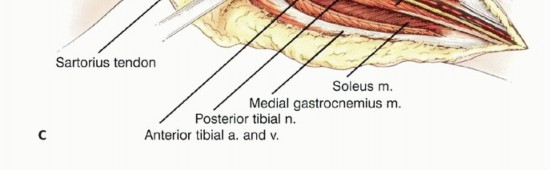

دور سديلة العضلة التوأمية الإنسية (Gastrocnemius Rotational Flap)

يُعد استخدام سديلة العضلة التوأمية الإنسية (عضلة الساق) عاملاً رئيسياً في تحقيق تغطية كافية للأنسجة الرخوة للطرف الصناعي واستعادة وظيفة آلية المد. تُنقل هذه العضلة لتدور إلى الأمام لتغطية الطرف الصناعي، مما يقلل بشكل كبير من خطر العدوى ومضاعفات الجروح، وهو ما كان يمثل تحدياً كبيراً في الماضي. يؤكد الأستاذ الدكتور محمد هطيف على أن هذه التقنية أصبحت إجراءً روتينياً وموثوقاً لضمان تغطية الطرف الصناعي وتقليل معدل العدوى ونخر السديلة والبتر الثانوي.

استكشاف الحفرة المأبضية والحزمة الوعائية

يجب استكشاف تفرع الشريان المأبضي مبكراً لتحديد ما إذا كان الورم قابلاً للجراحة، خاصة إذا كانت مكوناته في الأنسجة الرخوة تمتد خلفياً. إذا لم يكن هناك امتداد خلفي، يتم تعريض الفراغ المأبضي والتفرع عن طريق فصل العضلة التوأمية الإنسية وشق العضلة النعلية. يمكن تحديد الشريان المأبضي بسهولة وتتبعه بعيداً حول العضلة المأبضية. يجب توخي الحذر لتحديد وحماية جميع الفروع الوعائية الرئيسية.